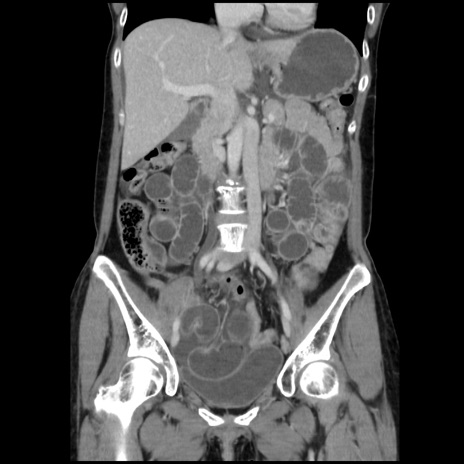

症例32(冠状断像)

【症例】40歳代 女性

【主訴】上腹部痛、嘔気・嘔吐

【現病歴】約9時間前頃から急に上腹部痛、嘔気、嘔吐が出現。改善しないため救急要請。

【既往歴】子宮頚癌(広汎子宮全摘術、放射線療法)、腸閉塞

【身体所見】腹部:平坦、軟、腸雑音亢進、上腹部を中心に腹部全体に圧痛あり。

【データ】WBC 8400、CRP 0.03